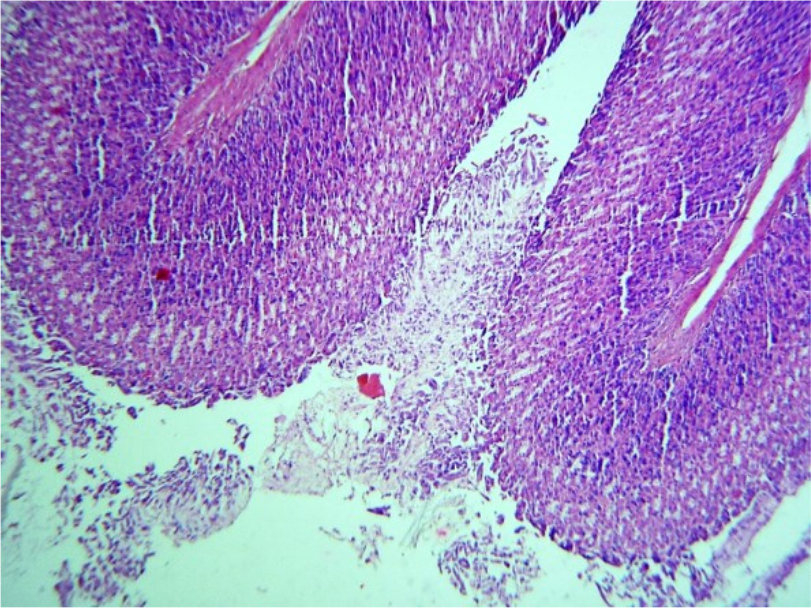

При проведении патоморфологического исследования животных из первой группы на 6-й день было выявлено, что стенка желудка имеет типичное строение, в слизистой оболочке присутствуют крупные фокусы дефекта - глубокого некроза и слущивания эпителия, смешанного со слизью (Рис. 3). Мышечная пластинка слизистой оболочки с очагами отека – мутная, гомогенизирована, имеет рыхлый вид. Подслизистая основа в состоянии деструкции, гомогенизирована, волокна стромы набухшие, разволокнены. Отек между волокнами обильные инфильтраты из эозинофилов, редких фибробластов. Отмечается, что инфильтрация эозинофилов распространяется и в мышечную пластинку (Рис.4). Кровеносные сосуды в состоянии гиперемии, микроциркуляторное русло в состоянии стаза

Рис. 3. Некроз и слущивание эпителия стенки желудка. Ув. ×400

Рис. 4. Отек с воспалительным эозинофильным инфильтратом Ув. ×200

Изменения на 6-й день у животных из первой группы свидетельствуют о присутствии крупных фокусов глубокого некроза и слущивания эпителия, смешанного со слизью. Подслизистая основа в состоянии деструкции, гомогенезирована.